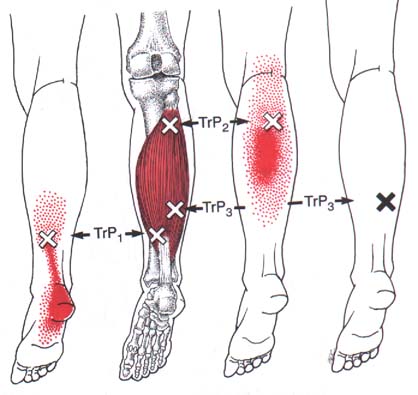

Trigger Point Dry Needling the Calf

Dry Needling Therapy as a Potential Treatment Option for Plantar Fasciitis Podiatry Today outlet, Trigger Point Dry Needling the Calf outlet, Dry Needling for Plantar Fasciitis Morningside Acupuncture NYC outlet, Dry Needling for Plantar Fasciitis Thoughts for Treatment Intricate Art Spine Body Solutions outlet, Dry Needling Therapy as a Potential Treatment Option for Plantar Fasciitis Podiatry Today outlet, What is Dry Needling and can it help me with my heel pain outlet, Dry Needling Manipulation to Treat Cure Plantar Fasciitis Foot Pain Intricate Art Spine Body Solutions outlet, Therafit Physical Therapy Dry Needling in Lowell MA outlet, Best Treatments for Plantar Fasciitis Back in the Game PT outlet, Trigger Point Dry Needling the Calf outlet, Does Dry Needling work for Plantar Fasciitis Acupuncture Dry Needling Prolotherapy in Tampa FL outlet, Therafit Inc Dry Needling for plantar fasciitis If you outlet, Dry Needling for Plantar Fasciitis Morningside Acupuncture NYC outlet, Dry Needling by Adelaide Podiatrists at Posture Podiatry outlet, Are You Sure It s Plantar Fasciitis Think Again. Rehab Renegade outlet, Plantar Fasciitis Get Active Physiotherapy outlet, Example of dry needle application to the right calf musculature. Photo. Download Scientific Diagram outlet, Dry Needling Brindabella Podiatry Book to see a Podiatrist today outlet, Cupping and Dry Needling For Plantar Fasciitis outlet, Dry Needling For Heel Pain In a Running Athlete Columbus Ohio Dr. Daniel Leonard outlet, Could dry needling be the answer to your aches and pains Bellarine Sports Medicine Centre outlet, Dry Needling what it is how it helped my running injuries TeriLyn Adams outlet, What is Dry Needling and can it help me with my heel pain outlet, Everything You Need to Know About Dry Needling for Plantar Fasciitis BenchMark Physical Therapy outlet, Dry Needling for Plantar Fasciitis A Path to Relief outlet, Physical Therapy Wellness Dry Needling This marathon runner came in for plantar fasciitis pain that limited her running distance to 3 miles. Plantar fasciitis is an umbrella. Instagram outlet, Dry Needling for Plantar Fasciitis Morningside Acupuncture NYC outlet, Dry Needling for Plantar Fasciitis Dry Needle Pain Relief outlet, Pod Fit Podiatry HOW DO YOUR CALF MUSCLES FEEL Pictured here is dry needling for a grumpy tibialis posterior muscle This is a key stabilising muscle that plays a outlet, Dry Needling for Plantar Fasciitis Dynamic Physiotherapy outlet, Dry Needling to the Plantar Fascia outlet, Complete Care Physiotherapy Osteopathy Wallan Fawkner Point Cook outlet, Dry Needling For Plantar Fasciitis Integrative Physical Therapy outlet, Are You Sure It s Plantar Fasciitis Think Again. Rehab Renegade outlet, Dry Needling for Plantar Fasciitis Relief outlet.

Dry Needling Therapy as a Potential Treatment Option for Plantar Fasciitis Podiatry Today outlet, Trigger Point Dry Needling the Calf outlet, Dry Needling for Plantar Fasciitis Morningside Acupuncture NYC outlet, Dry Needling for Plantar Fasciitis Thoughts for Treatment Intricate Art Spine Body Solutions outlet, Dry Needling Therapy as a Potential Treatment Option for Plantar Fasciitis Podiatry Today outlet, What is Dry Needling and can it help me with my heel pain outlet, Dry Needling Manipulation to Treat Cure Plantar Fasciitis Foot Pain Intricate Art Spine Body Solutions outlet, Therafit Physical Therapy Dry Needling in Lowell MA outlet, Best Treatments for Plantar Fasciitis Back in the Game PT outlet, Trigger Point Dry Needling the Calf outlet, Does Dry Needling work for Plantar Fasciitis Acupuncture Dry Needling Prolotherapy in Tampa FL outlet, Therafit Inc Dry Needling for plantar fasciitis If you outlet, Dry Needling for Plantar Fasciitis Morningside Acupuncture NYC outlet, Dry Needling by Adelaide Podiatrists at Posture Podiatry outlet, Are You Sure It s Plantar Fasciitis Think Again. Rehab Renegade outlet, Plantar Fasciitis Get Active Physiotherapy outlet, Example of dry needle application to the right calf musculature. Photo. Download Scientific Diagram outlet, Dry Needling Brindabella Podiatry Book to see a Podiatrist today outlet, Cupping and Dry Needling For Plantar Fasciitis outlet, Dry Needling For Heel Pain In a Running Athlete Columbus Ohio Dr. Daniel Leonard outlet, Could dry needling be the answer to your aches and pains Bellarine Sports Medicine Centre outlet, Dry Needling what it is how it helped my running injuries TeriLyn Adams outlet, What is Dry Needling and can it help me with my heel pain outlet, Everything You Need to Know About Dry Needling for Plantar Fasciitis BenchMark Physical Therapy outlet, Dry Needling for Plantar Fasciitis A Path to Relief outlet, Physical Therapy Wellness Dry Needling This marathon runner came in for plantar fasciitis pain that limited her running distance to 3 miles. Plantar fasciitis is an umbrella. Instagram outlet, Dry Needling for Plantar Fasciitis Morningside Acupuncture NYC outlet, Dry Needling for Plantar Fasciitis Dry Needle Pain Relief outlet, Pod Fit Podiatry HOW DO YOUR CALF MUSCLES FEEL Pictured here is dry needling for a grumpy tibialis posterior muscle This is a key stabilising muscle that plays a outlet, Dry Needling for Plantar Fasciitis Dynamic Physiotherapy outlet, Dry Needling to the Plantar Fascia outlet, Complete Care Physiotherapy Osteopathy Wallan Fawkner Point Cook outlet, Dry Needling For Plantar Fasciitis Integrative Physical Therapy outlet, Are You Sure It s Plantar Fasciitis Think Again. Rehab Renegade outlet, Dry Needling for Plantar Fasciitis Relief outlet.